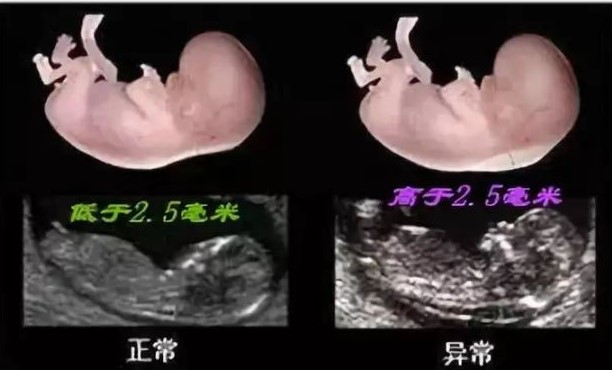

孕妈们在怀孕11~13+6周时进行早孕期NT检查,完成NT检查之后,孕妈们通常会注意到报告中“胎儿NT厚度为XX mm”,这是孕早期NT检查的重要结果。NT的中文译名是胎儿颈项透明带(Nuchal Translucency,简称NT),指孕早期出现在胎儿颈后部的液体透明带。宝宝NT值<2.5 mm,考虑NT筛查低风险;当NT≥2.5 mm,就需要孕妈们关注了, NT越厚,胎儿的风险越高。